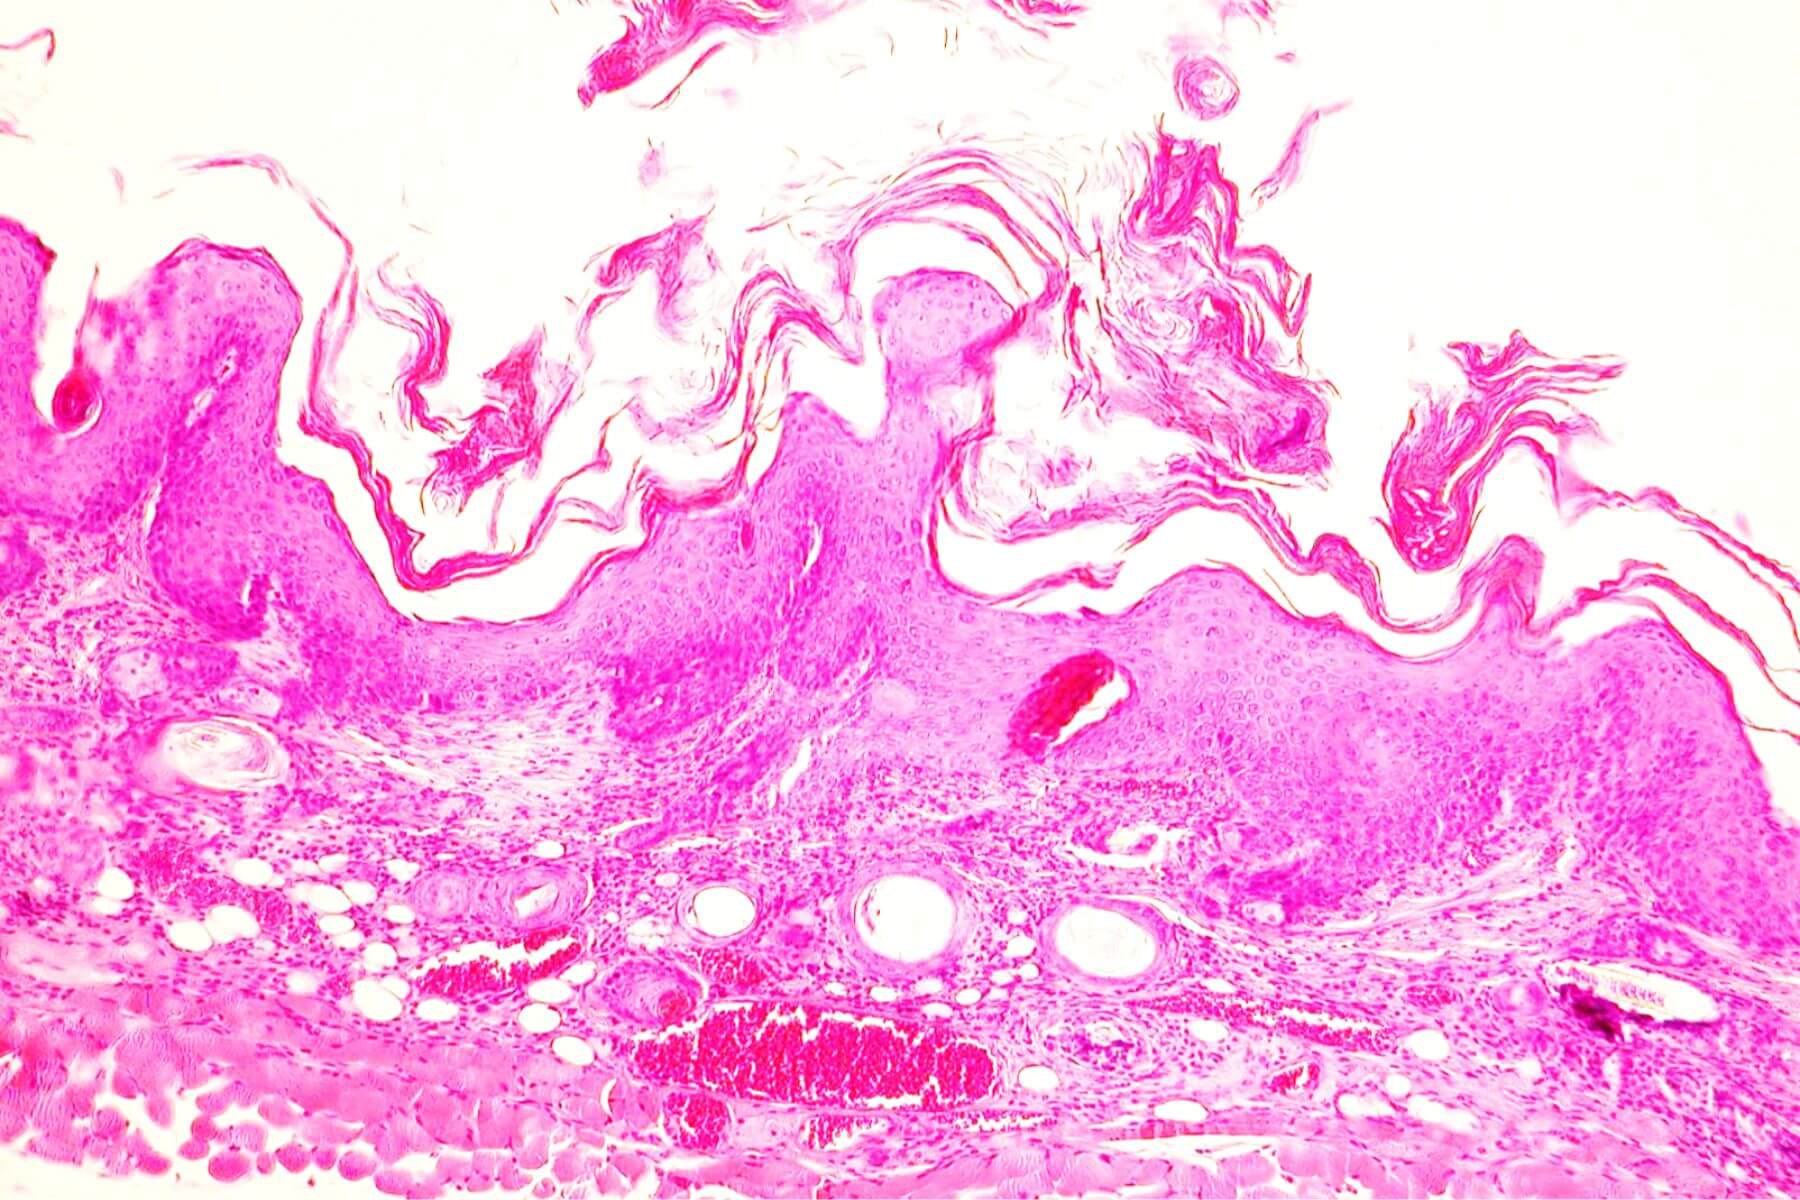

Immunohistochemistry, Immunofluorescence, and Histology

We have four areas of expertise to support the development of your drugs and medical devices: inflammatory skin diseases (Psoriasis, Atopic Dermatitis, Eczema…), wound healing (acute and chronic wounds), skin grafting (skin substitutes, organoids, biomimetic constructs…), and dermal toxicity (acute, sub‑chronic, and chronic).